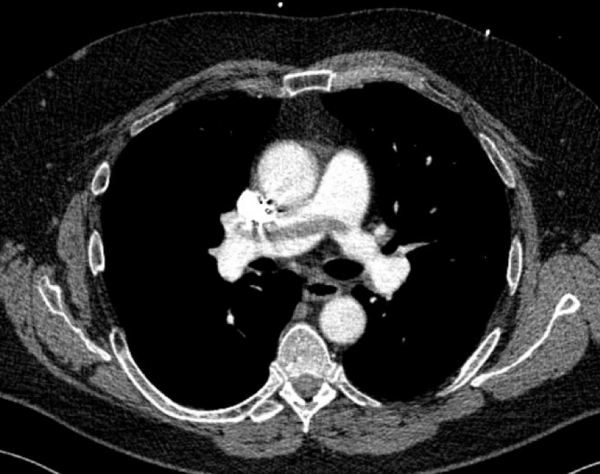

CT angiography of the chest with intravenous contrast was performed.

There is a filling defect straddling the bifurcation of the pulmonary trunk extending into the distal branches of the right lower, right middle, right upper and left upper lobe consistent with a saddle embolism. Bedside echocardiography revealed mild concentric hypertrophy, an ejection fraction of 60%, with normal right ventricular global systolic function, with no evidence for an elevated right ventricular systolic pressure.